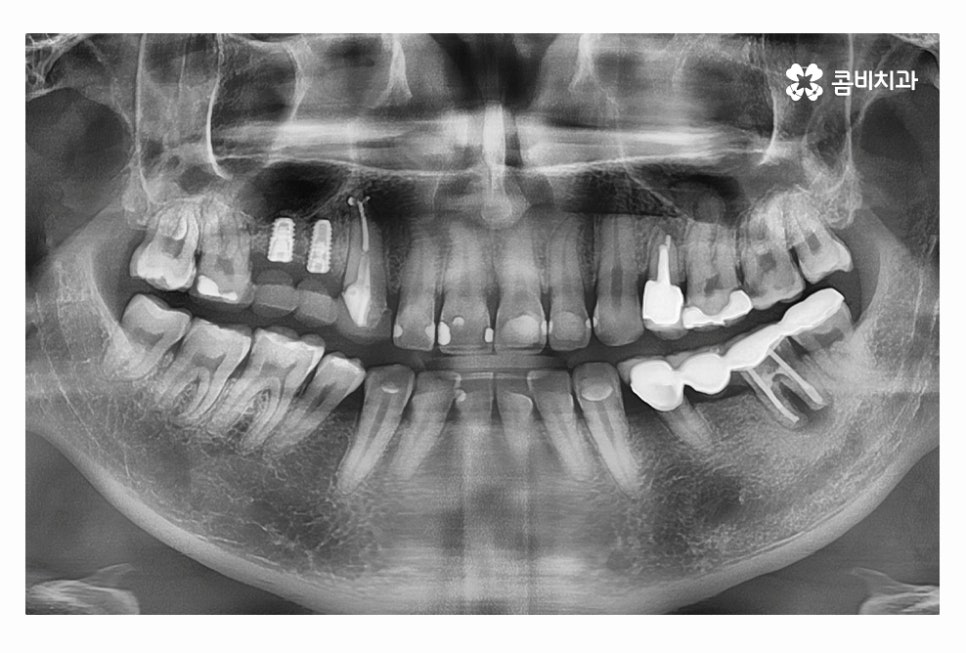

임플란트의 원리는 잇몸에 임플란트를 식립하고 골유착 과정을 통해서

단단하게 인공치근이 고정이 되고 보철물을 연결하여

자연치아의 기능 거의 대부분을 회복할 수 있는데요.

임플란트의 치료 계획은 치아를 잃게 된 원인부터 잇몸 상태,

전신질환 여부, 회복력 등을 고려하여 1:1로 맞춤 치료 계획을 세우며

자연치아를 대체하는 치료인 만큼 치료 결과도 중요하지만

수명을 오랫동안 건강하게 유지하는 것이 관건이라고 할 수 있는데요.